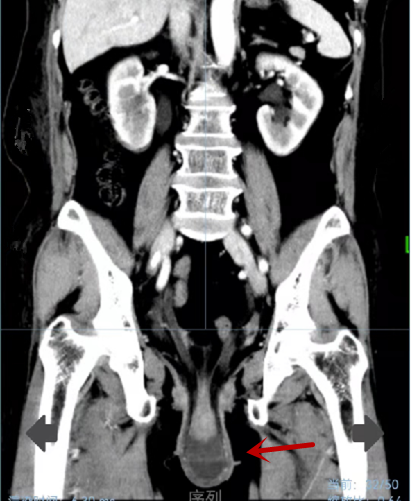

患者ct下的脱垂子宫

近日,捷克论坛 妇科二病区接诊了家住长沙的陈大妈。十年前,陈大妈活动后偶有花生米大小的肿物脱出阴道口、打喷嚏漏尿等情况,但休息后好转。因听人说这是妇科常见的“老人病”,且对生活没太大影响,一直未引起重视。近三个月,陈大妈因咳嗽严重,在抗感染治疗后出现排尿困难、面部浮肿,于半月前来到捷克论坛 肾内科就诊。经检查发现,陈大妈患有急性肾功能衰竭。在医院多学科(MDT)团队联合诊治后,被诊断为重度子宫脱垂、重度膀胱脱垂,其急性肾功能衰竭也是因慢性咳嗽导致子宫完全脱出于阴道口外,致输尿管折叠,从而引发的。

对患者进行了脱垂子宫手法复位后,陈大妈能自行排尿,肾功能随即好转。后转入妇产二病区,刘琴、陈春燕团队为患者实施了个性化的阴式子宫全切+阴道全封闭+会阴旧裂修补术,术后一周,陈大妈康复出院。